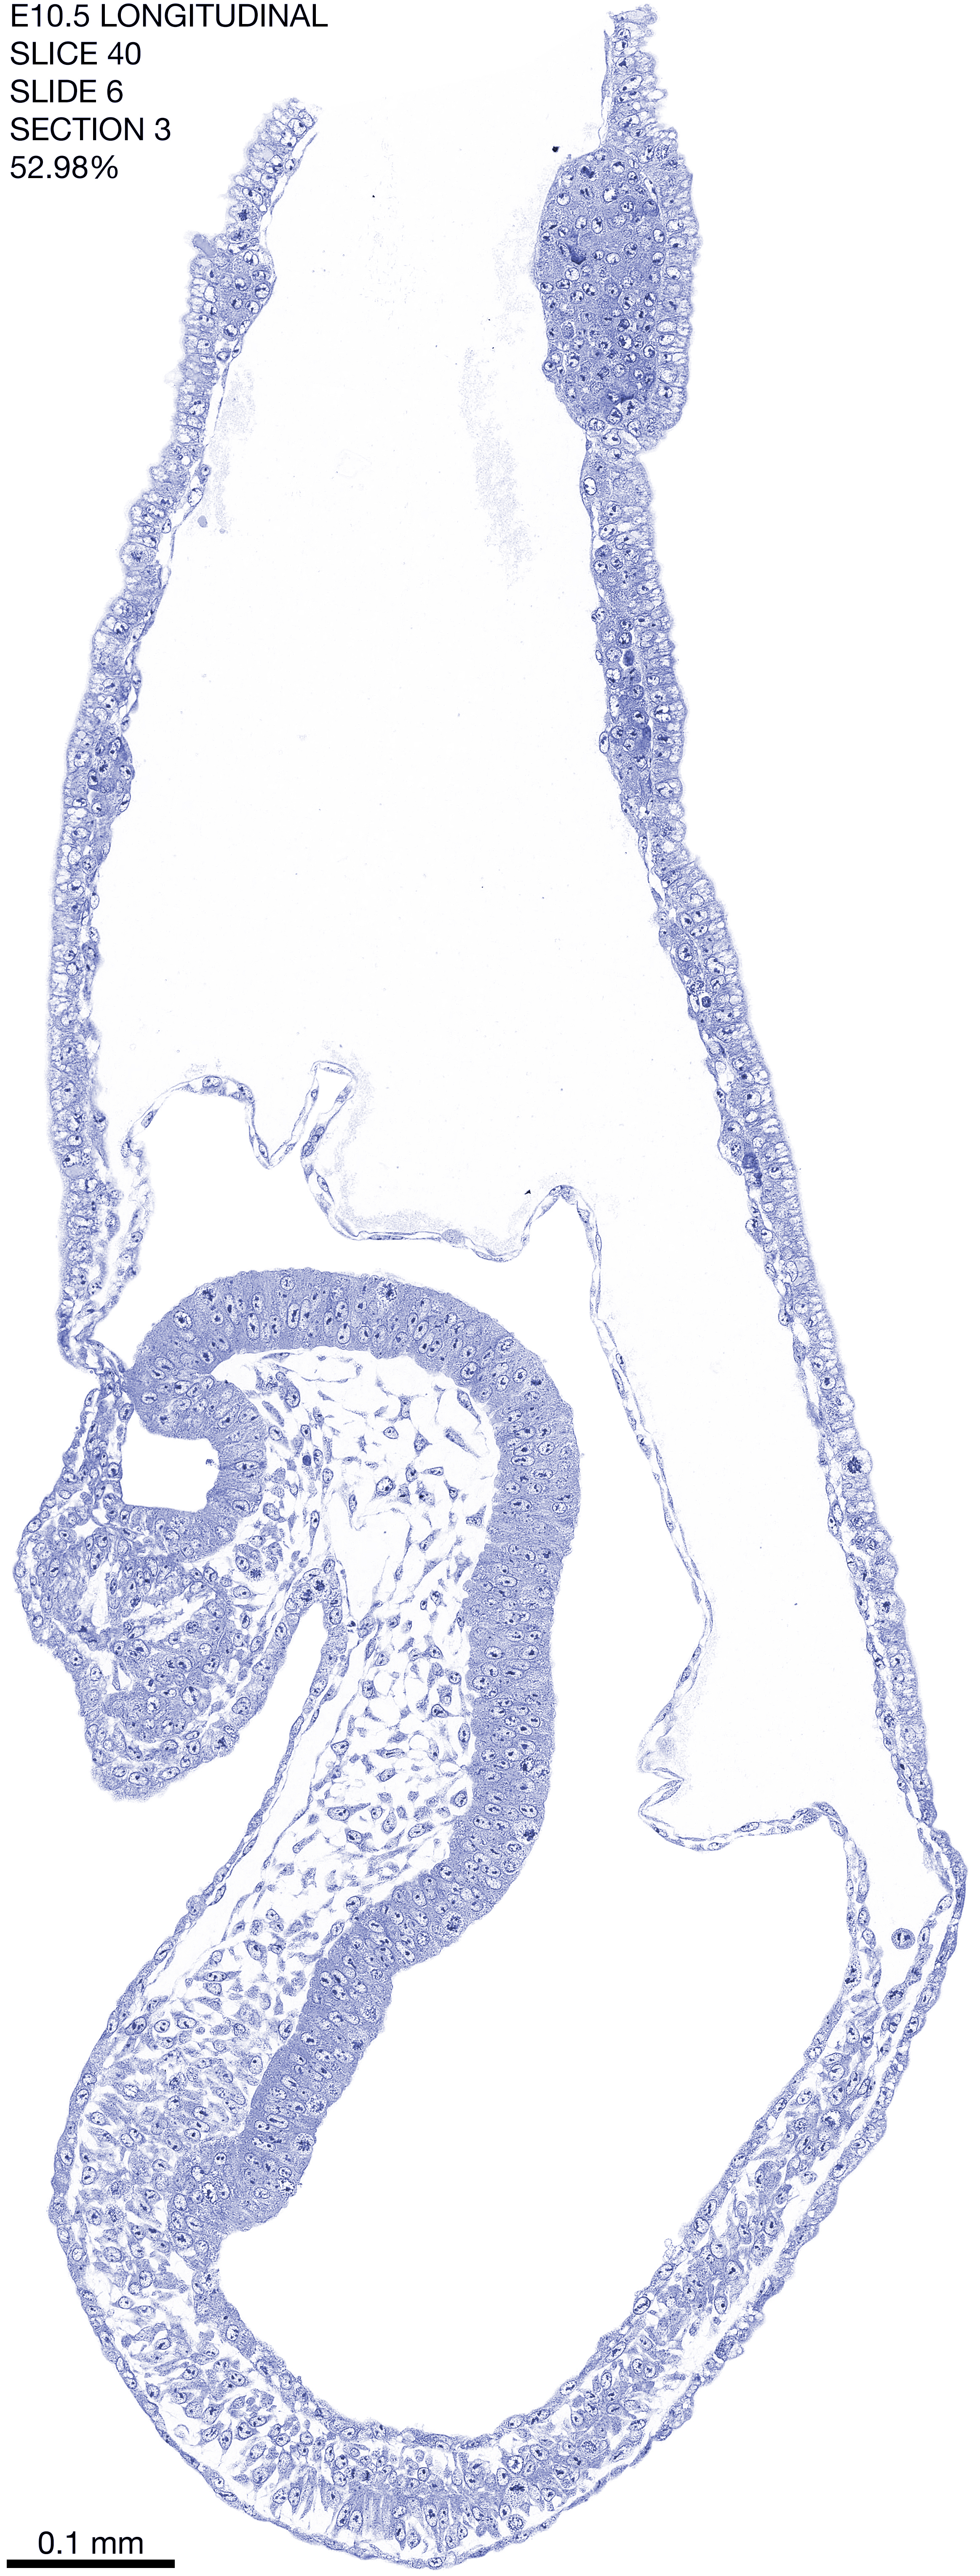

E10.5 Longitudianal Archive This page contains jpg files of ALL SLICES (each 3µm thick) that were scanned of the E10.5 longitudinally cut specimen. Download: Large | High Res Download: Large | High Res Download: Large | High Res Download: Large | High Res Download: Large | High Res Download: Large | High Res Download: Large | High Res Download: Large | High Res Download: Large | High Res Download: Large | High Res Download: Large | High Res Download: Large | High Res Download: Large | High Res Download: Large | High Res Download: Large | High Res Download: Large | High Res Download: Large | High Res Download: Large | High Res Download: Large | High Res Download: Large | High Res Download: Large | High Res Download: Large | High Res Download: Large | High Res Download: Large | High Res Download: Large | High Res Download: Large | High Res Download: Large | High Res Download: Large | High Res Download: Large | High Res Download: Large | High Res Download: Large | High Res Download: Large | High Res Download: Large | High Res Download: Large | High Res Download: Large | High Res Download: Large | High Res Download: Large | High Res Download: Large | High Res Download: Large | High Res Download: Large | High Res Download: Large | High Res Download: Large | High Res Download: Large | High Res Download: Large | High Res Download: Large | High Res Download: Large | High Res Download: Large | High Res Download: Large | High Res Download: Large | High Res Download: Large | High Res Download: Large | High Res Download: Large | High Res Download: Large | High Res Download: Large | High Res Download: Large | High Res Download: Large | High Res Download: Large | High Res Download: Large | High Res